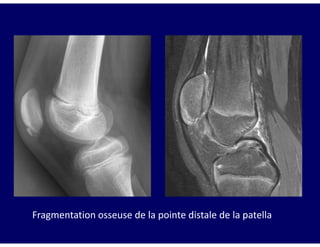

Ostéochondrose du pôle inférieur de la Patella

Adolescent: 10-14ans

Pathogénie semblable à celle de la maladie d’Osgood

Schlatter (microtraumatismes à répétition) fracture-

avulsion de la pointe de la patella

Maladie de Sinding-Larsen-Johansson

Douleur + tuméfaction des tissus mous en regard du pôle

inférieur de la patella

Radiographie: tuméfaction + fragmentation osseuse de la

pointe distale de la patella

Évolution: guérison en 3 à 12 mois

Fragmentation osseuse de la pointe distale de la patella